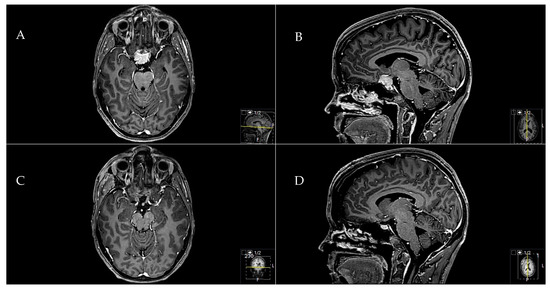

2.5.1. Exemplary Case One